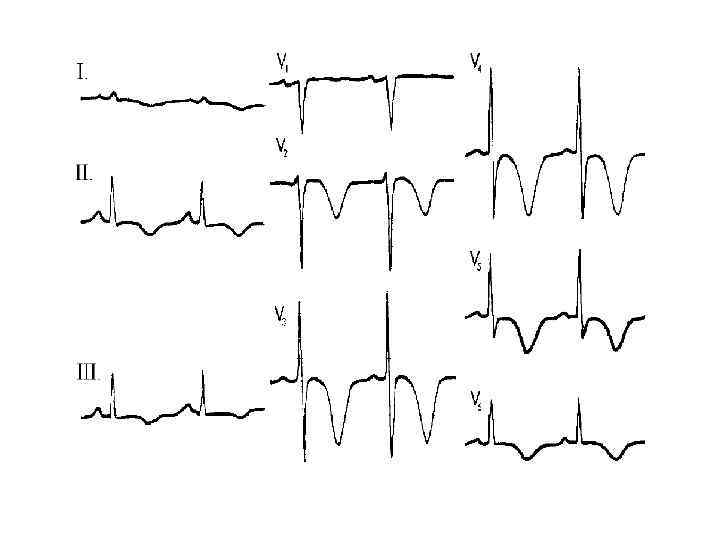

Рестриктивная кардиомиопатия Клиника и диагностика • Первичный амилоидоз • - Диагностика Моноклональная иммуноглобулинопатия – 90 % б-х Гипогаммаглобулинемия Плазмацитоз в костном мозге > 50% б-х Тромбоцитоз - 10% б-х На ЭКГ – «псевдоинфарктные изменения» , нарушения сердечного ритма и проводимости На ЭХОКГ – утолщение стенок левого и правого желудочка, утолщение эндокарда клапанов, регургитация, жидкость в перикарде, расширение предсердий, выраженное нарушение расслабления

Рестриктивная кардиомиопатия Клиника и диагностика • Первичный амилоидоз • - Диагностика Моноклональная иммуноглобулинопатия – 90 % б-х Гипогаммаглобулинемия Плазмацитоз в костном мозге > 50% б-х Тромбоцитоз - 10% б-х На ЭКГ – «псевдоинфарктные изменения» , нарушения сердечного ритма и проводимости На ЭХОКГ – утолщение стенок левого и правого желудочка, утолщение эндокарда клапанов, регургитация, жидкость в перикарде, расширение предсердий, выраженное нарушение расслабления

Гипертрофическая кардиомиопатия • • • одышка при физической нагрузке боли в груди, которые могут быть стенокардитического характера сердцебиение и синкопальные состояния внезапная сердечная смерть систолический шум, который может быть различным - от средне- до позднесистолического, и IV сердечный тон, интенсивность систолического шума возрастает, когда больной встает, а также в фазе напряжения при пробе Вальсальвы электрокардиографические признаки гипертрофии левого предсердия и левого желудочка, зубцы Q в отведениях V 4 -V 6 , Q в II, III, AVF отведениях, появление которых связывают с гипертрофией верхней трети межжелудочковой перегородки

Гипертрофическая кардиомиопатия • • • одышка при физической нагрузке боли в груди, которые могут быть стенокардитического характера сердцебиение и синкопальные состояния внезапная сердечная смерть систолический шум, который может быть различным - от средне- до позднесистолического, и IV сердечный тон, интенсивность систолического шума возрастает, когда больной встает, а также в фазе напряжения при пробе Вальсальвы электрокардиографические признаки гипертрофии левого предсердия и левого желудочка, зубцы Q в отведениях V 4 -V 6 , Q в II, III, AVF отведениях, появление которых связывают с гипертрофией верхней трети межжелудочковой перегородки